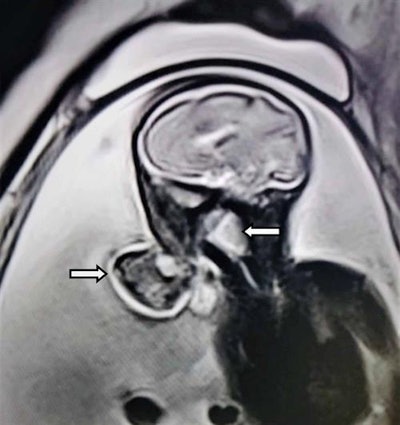

An MRI scan was performed to obtain better characterization of the tumor and to evaluate the association between the mass and surrounding structures. The MR images revealed a mixed-intensity mass with a stalk protruding through the jaws into the amniotic fluid. The internal part of the mass started at the hard palate and filled a large part of the oropharynx. The mass wasn't associated with any central nervous system anomaly, the authors wrote.